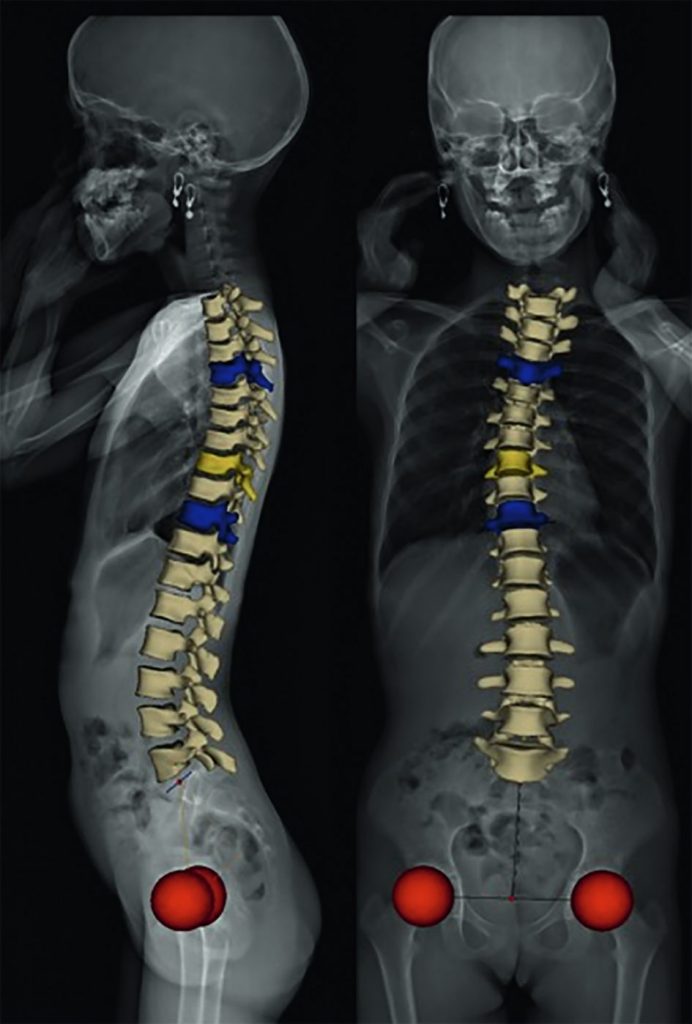

Le système EOS®, de par la qualité de ses clichés, la réduction de son irradiation (par rapport aux systèmes conventionnels) et ses possibilités de mesure 3D, a pris une place majeure dans le suivi des scolioses (figures 119.4 et 119.5).

Fig. 119.5 Enfant de 9 ans. Scoliose thoracique droite idiopathique. Modélisation 3D après acquisition d’une face et d’un profil sur système Eos®.

Les vertèbres limites sont en bleu, la vertèbre sommet en jaune et les têtes fémorales en rouge. Ceci permet une mensuration 3D de l’angle de Cobb plus proche de la réalité, la scoliose étant une déformation tridimensionnelle.

Source : CERF, CNEBMN, 2022.